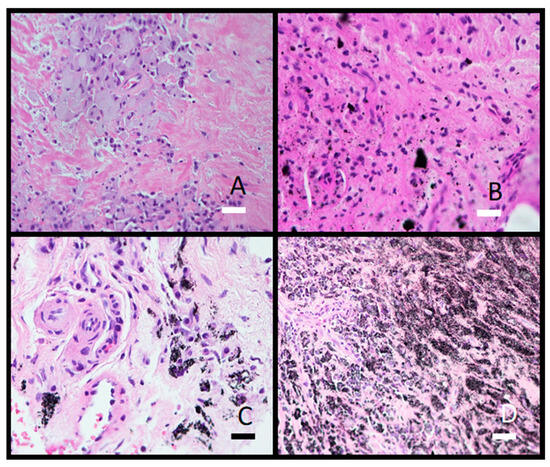

Histological analysis showed granulomatous tissue in a periprosthetic membrane (bone marrow) with macrophages and giant cells. Macrophages contained varying amounts of metal particles in the cytoplasm, which appeared as a grey-blue staining of the cytoplasm or visible black particles (Figure 9). In one case, severe metallosis was found. Besides macrophages and giant cells, lymphocyte infiltration was seen as diffuse infiltration or as small perivascular cuffs (Figure 10).

Figure 10.

Photomicrograph illustrations of lymphocytic infiltrate in periprosthetic membrane. (A) Diffuse distributed lymphocytes (obj. mag. 40×) and (B) small perivascular lymphocytic cuff (obj. mag. 20×). Black bar = 50 μm and white bar = 100 μm.

Metal particles can trigger an inflammatory response in the tissue and the presence of immune cells like macrophages and lymphocytes. Lymphocytes are a common finding in histological examinations of tissue surrounding prosthetic implants. They may be present within the granulomatous or connective tissue, around blood vessels, or in areas of inflammation. In addition to the diffusely distributed lymphocytes in the periprosthetic tissue, numerous smaller perivascular clusters of lymphocytes were also seen in this study. The presence of perivascular lymphocytes indicates an immune reaction to the prosthetic implant or its components. The immune response is the body’s way of reacting to foreign material, potentially including metal particles or other constituents of the implant. The number of lymphocytes increases in the periprosthetic tissues with increasing time of implant service [27]. However, the tissue image analysis cannot differentiate finer, potentially metal-induced tissue changes [28].